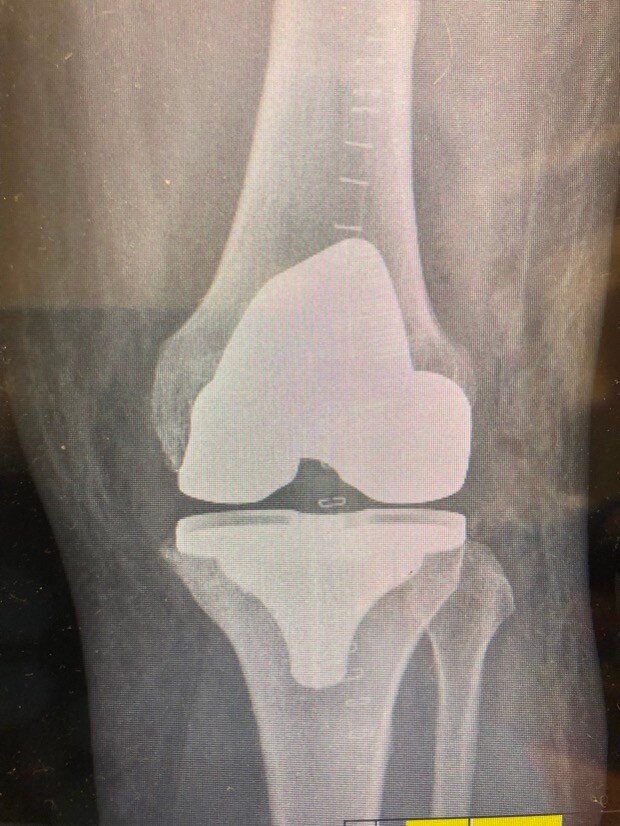

1. Evening TT’ers I’m one week into recovery from having total knee replacement surgery on my left knee. I’m wondering if anyone else out there has had the same surgery and can provide some advice on how long it took after surgery before you were back on the golf course or at least swinging a club. Are there any pitfalls I should avoid? All advice welcome including tongue in cheek to cheer me up!!! Cheers………..Steve

Post Image

3. Stephen, I've been there - I've got similar X-rays, though mine have random bits of metal from earlier ACL's. Right knee for me. Right knee is "better" as the loading through the swing is more intense on the left knee for right handers. One week in can be a low point. No point in being a hero - take whatever painkillers they give you!! Stairs will be an issue for some considerable time I'm afraid. You will, however, be able to use stairs to strengthen your muscles. Be diligent about your physio and to get access to an exercise bike of some description! When allowed, I did lots of walking and found it helped. I had my op in the November and was ready for the Driving Range the following March. Some say they were back on the golf course six weeks after the op - I would consider that to be a very risky strategy. It's a major reconstruction and it takes time to heal. The numbness wears off eventually but don't expect it to be exactly like a natural knee - it's good, but it's not that good! Oh, and be prepared to be stopped by Security at every airport - You'll set of the metal detector alarms!!